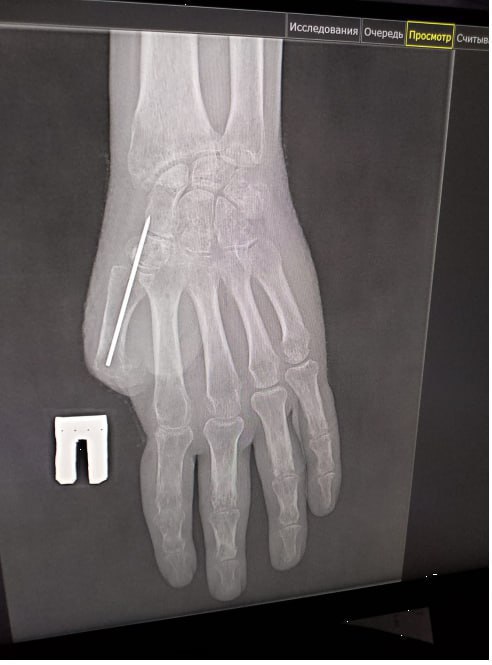

Боец потерял большой палец руки в результате взрыва. Первую операцию мужчине провели ещё в начале года. Сегодня готово основание для фаланги.

Как сообщает региональный миндзрав, специалисты сформировали первый луч кисти и выполнили пластику «китайским лоскутом» – пересадили на кисть лоскут ткани с собственными сосудами. Такая методика гарантирует полноценное кровоснабжение и надежное приживление.